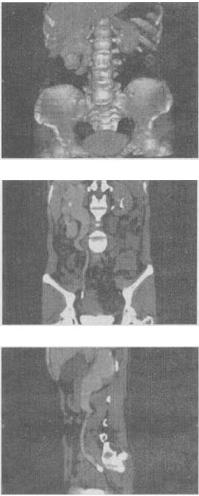

- 单项选择题 女,42岁,反复右下腹痛1个月,CT检查如图所示,下列诊断正确的是()。

A、右侧输尿管上段结石,其上方输尿管扩张积水

B、右侧输尿管中段结石,其上方输尿管扩张积水

C、右侧输尿管下段结石,其上方输尿管扩张积水

D、右侧输尿管下段结核,其上方输尿管扩张积水

E、右侧输尿管下段炎性狭窄,其上方输尿管扩张积水

- C